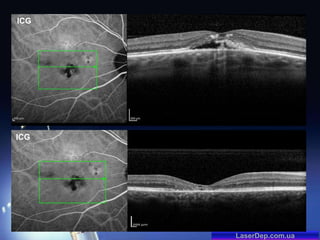

Ретинальная ангиоматозная пролиферация

RAP (Retinal angiomatous proliferation)

Vis OD 0,5 н.к.

ICG